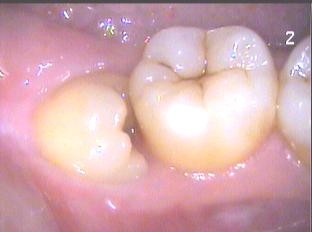

前倾阻生智齿,它的牙冠向前倾倒,直抵邻牙颈部,无论在口腔内还是X线片上都很直观,在形态上,跟警察跪压在黑人颈部非常相似,而且造成的后果也基本相同。

最后,回到重点,关于前倾阻生智齿,最佳的应对方案是什么呢?除了少数特例可因正畸需求而予以“扶正”以外,绝大多数前倾智齿,只要一发现,早期果断拔除是明智的选择,要尽量在其邻牙受损之前解决,切不可置之不理,任其野蛮生长,那相当于给它一片酝酿和蓄积破坏力的土壤,这种破坏力随着时间的延续将越来越深刻,越来越顽固,越来越难以改变。